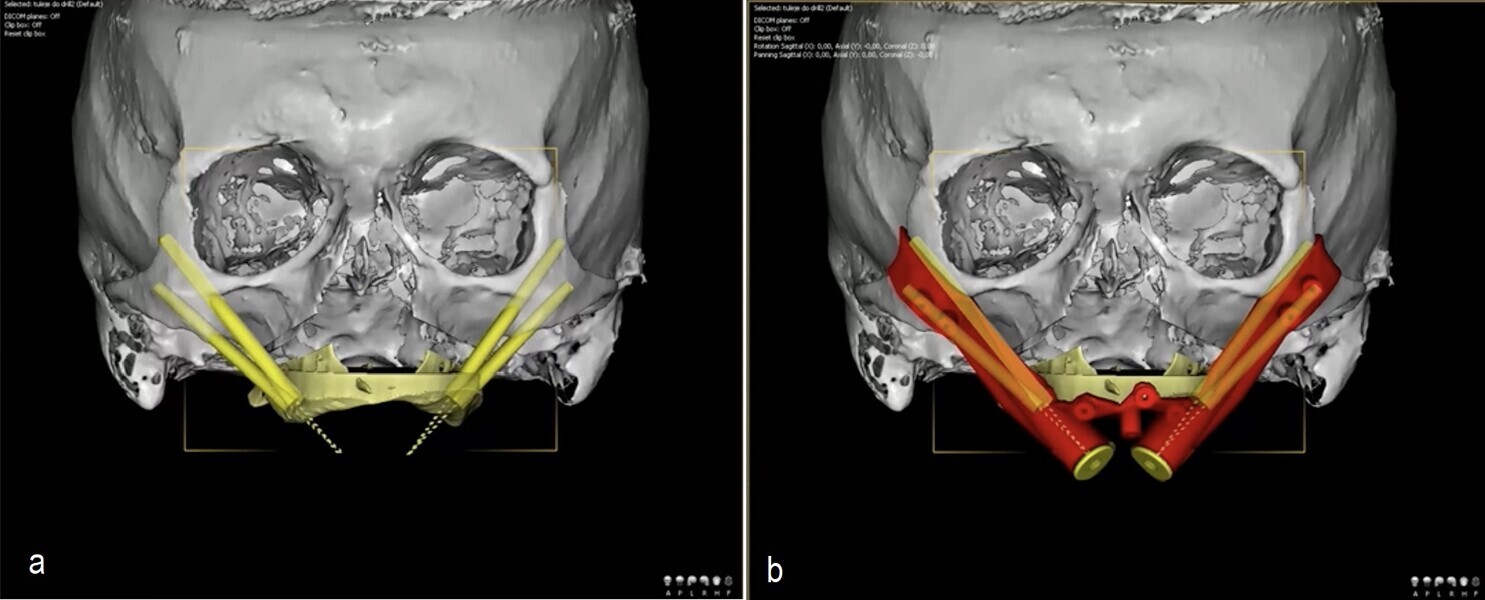

During surgery, I use two 3D-printed surgical guides: one affixed before the osteotomy to guide implant and anchor pin positioning, and the second used after repositioning the maxilla to confirm implant alignment and skeletal placement. This workflow enhances reproducibility and reduces human error, the only variable being the quality of diagnostic data.

I recently applied this technique in the treatment of a 69-year-old patient with longstanding edentulism and advanced maxillary bone loss. The procedure, planned entirely with DDS-Pro, allowed for accurate implant placement and maxillary repositioning (Figs. 1–4). Carried out under general anaesthesia, the surgery took approximately 2 hours and was completed without complication (Figs. 5 & 6). The surgical guides functioned exactly as expected, leading to a stress-free operation.